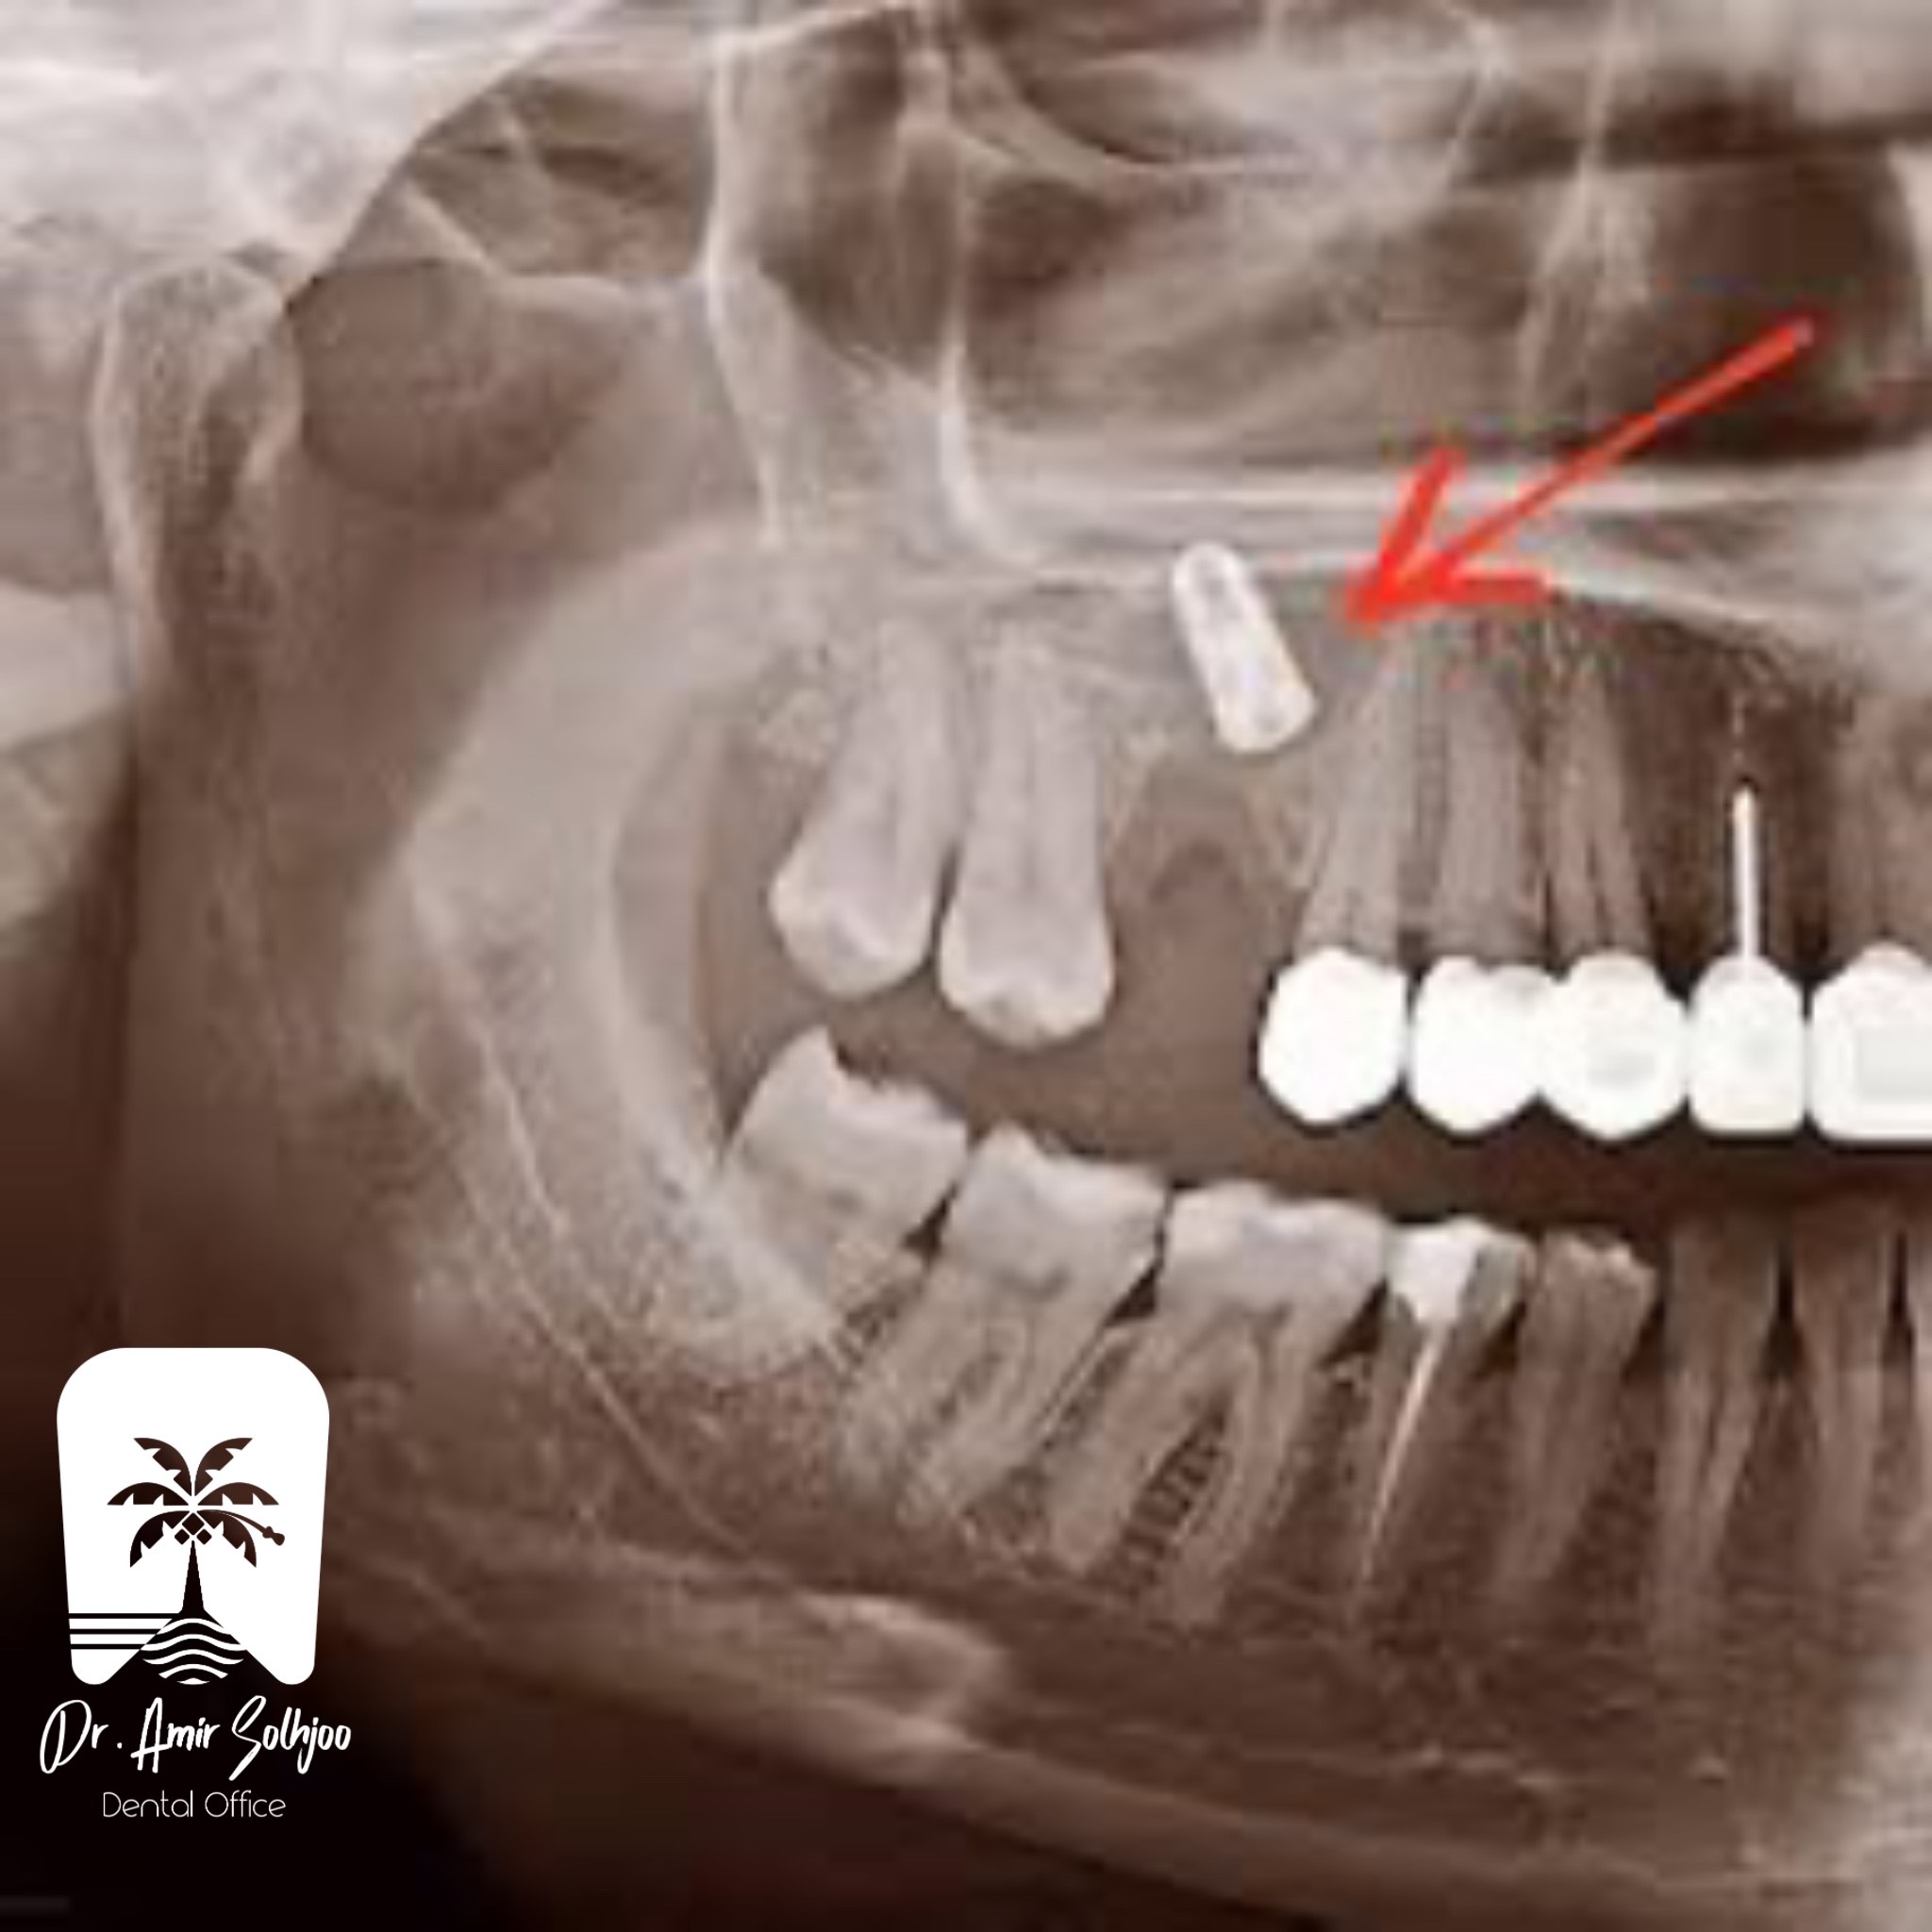

Iranian implant photo